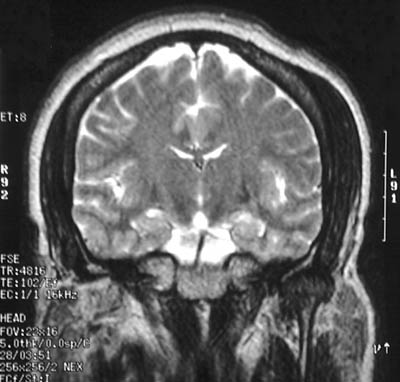

| In the axial FSE proton MRI scan of the head above can be seen marked temporalis muscle hypertrophy, particularly on the left. A coronal T2 weighted view is seen below. The temporalis muscle acts to close the jaw, bringing the mandible upward to the maxilla. Temporomandibular joint problems with difficulty chewing could produce such hypertrophy. Bruxism, which is gnashing, grinding, or clenching one's teeth, perhaps as a result of relatives who came to visit and stayed too long, could produce a similar result. |